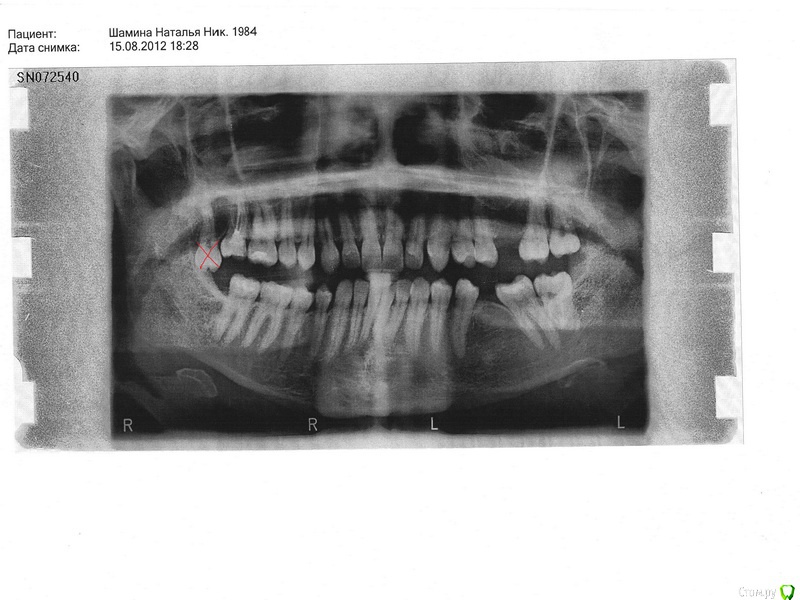

nachik Опубликовано 13 января, 2015 Поделиться Опубликовано 13 января, 2015 Добрый день. Ношу брекеты с октября 2012 года (2 года 4 месяца). Цель установки: освободить место под дальнейшую имплантацию. Вставлять имплант при кормлении грудью не советует врач по причине того, что возможно придется пить антибиотики. Нижняя челюсть зашинирована в ноябре 2013 года, верхняя – в ноябре 2014 года.Мои вопросы:1.Возможно ли мне снять брекеты сейчас и носить несъемные ретейнеры и съемные (или капы), а поставить импланты уже после завершения кормления грудью? Мой ортодонт предлагает снять систему только после установки зубов, а это еще год-полтора. 2. Можно ли изменить ситуацию с верхними единичками? Ортодонт говорит, что один зуб стерся неравномерно, вот по-этому так и останется.Снимок до установки. Фото сейчас. Ссылка на комментарий